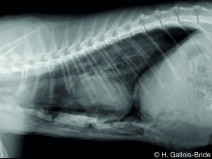

• VETOALP 2025 - Programme entier - "Les défis de la prise en charge de l’animal polytraumatisé : de l’urgence à la chirurgie"

Rejoignez-nous à Chamonix du 9 au 13 mars 2025, pour cette nouvelle édition de VETOALP consacrée aux défis de la prise en charge de l’animal polytraumatisé, de son admission en urgence à la chirurgie !

Pour cette édition, l’AFVAC Rhône-Alpes accueille le Groupe d’Étude d’Urgence et Réanimation (GEUR) et le Groupe d’Étude de Chirurgie (GEC), afin d’établir un dialogue au sommet.

Du 9 au 13 mars 2025

Chamonix-Mont-Blanc (74400)

Chirurgie

Traumatologie

Urgence et Réanimation

Rhône-Alpes, G.E.C., G.E.U.R.